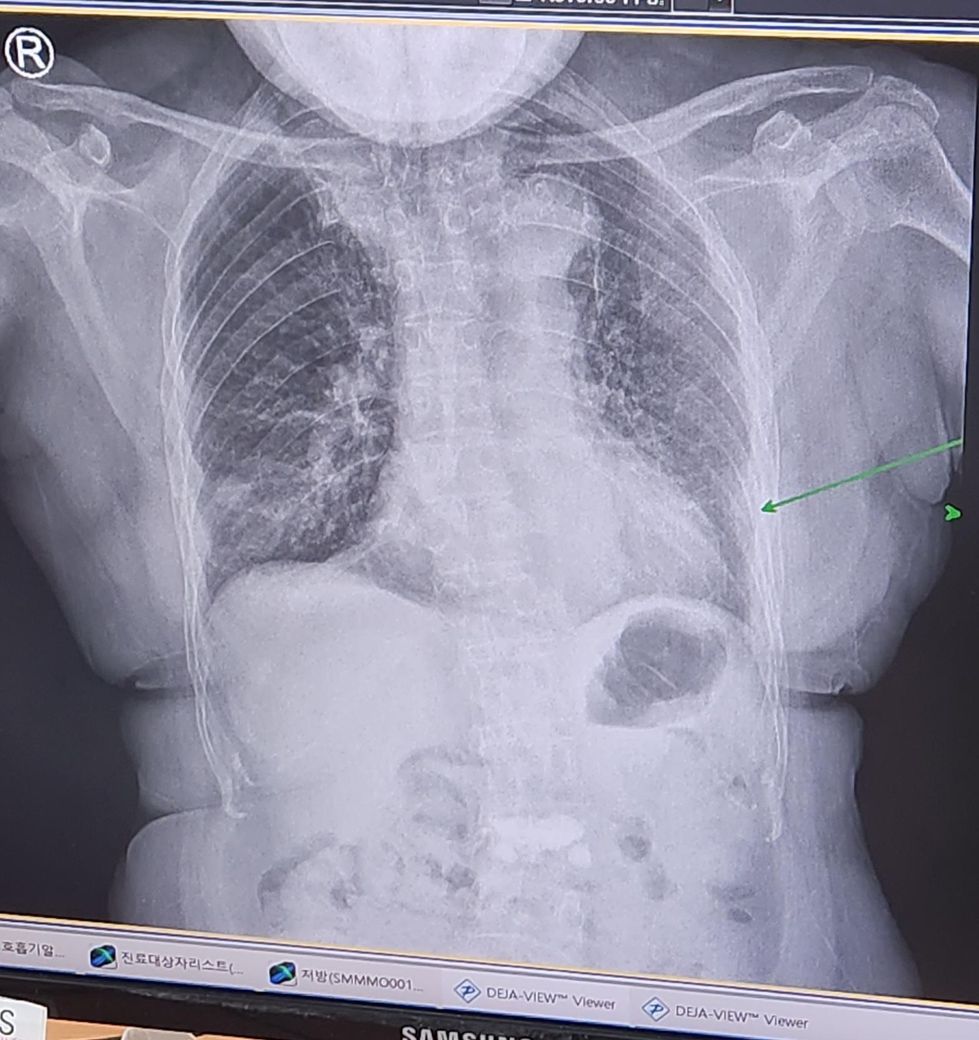

폐렴으로 통원 5일후 엑스레이 변화입니다

선생님께서는 많이없어졌다하셨는데

저는 잘 차이를 모르겠어서요.

위에사진이 5일전

아래가 오늘 5일후 사진입니다

초록색화살표는 폐렴이 아니라 하셨는데

맞을까요?

안녕하세요. 아하의 의료상담 전문가 의사 김민성입니다. 질문자분께서 보내주신 엑스레이 사진을 보고 폐렴의 변화에 대해 궁금해하시는 것 같아요. 엑스레이 해석은 경험이 많이 필요한 부분이라 직접적인 차이를 확인하기 어려우실 수 있습니다. 그렇지만 폐렴의 경우에는 엑스레이에서의 변화뿐만 아니라 임상적인 증상과 환자의 전반적인 상태도 함께 고려해야 합니다.

질문자분의 담당 의사 선생님께서 많이 나아졌다고 하신 것이라면, 엑스레이 상의 변화와 더불어 증상의 호전이 있었다고 판단하셨을 가능성이 높습니다. 약을 2일만 더 복용하라고 하신 것도 이러한 상태 변화를 감안한 계획일 것입니다. 초록색 화살표 부분이 폐렴이 아니라는 설명도 전문가의 판단일 가능성이 높으니 너무 걱정하지 않으셔도 될 것 같아요.

정확한 진단과 치료 계획은 사진이나 증상 설명만으로 결정하기 어려운 만큼, 병원에서의 설명을 신뢰하시면서 꾸준히 상태를 체크하시는 것이 중요합니다.

엑스레이 관련해서도 그닥 큰 차이는 없어 보이는데 정확하게 파악하시려면 영상의학과 전문의에게 의뢰하시는게 좋습니다

결론적으로 폐렴 치료 후 5일 동안의 엑스레이 변화를 담당의가 긍정적으로 평가했다면 이는 상태가 개선되고 있음을 의미 할 확률이 큽니다. 약을 2일만 더 복용하고 종료하는 것은 보통 담당 의사가 평가한 치료 상태가 충분히 좋아졌다는 판단을 기반으로 한 걸 거구요.